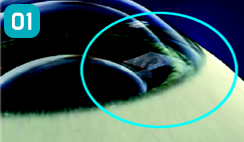

렌즈 삽입기구를 이용하여 절개창을 통해 ICL을 삽입합니다.

삽인된 ICL을 렌즈훅(Hook)을 이용해 홍채 뒤에 위치시킵니다.